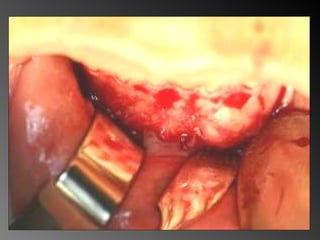

Exame complementares RadiografiaPanorâmica; Radiografia Oculsal; Teste de Vitalidade; Punção Exploratória; Biópsia incisional.

Aspecto Histopatológico FonteAllan Giovanini Lâmina 1

Lâmina 2 FonteAllan Giovanini